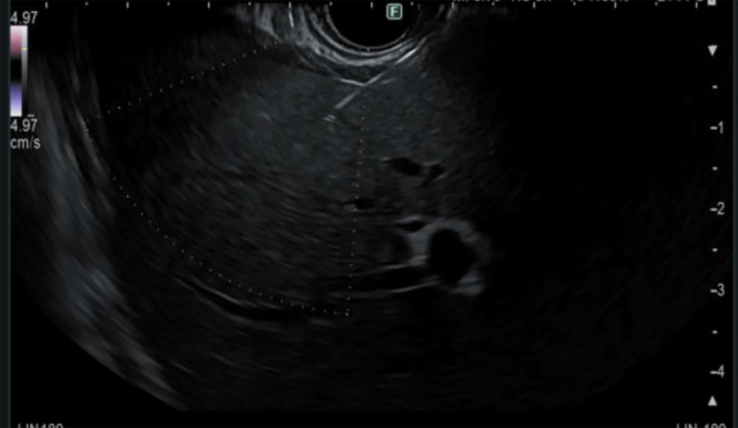

Abstract Image